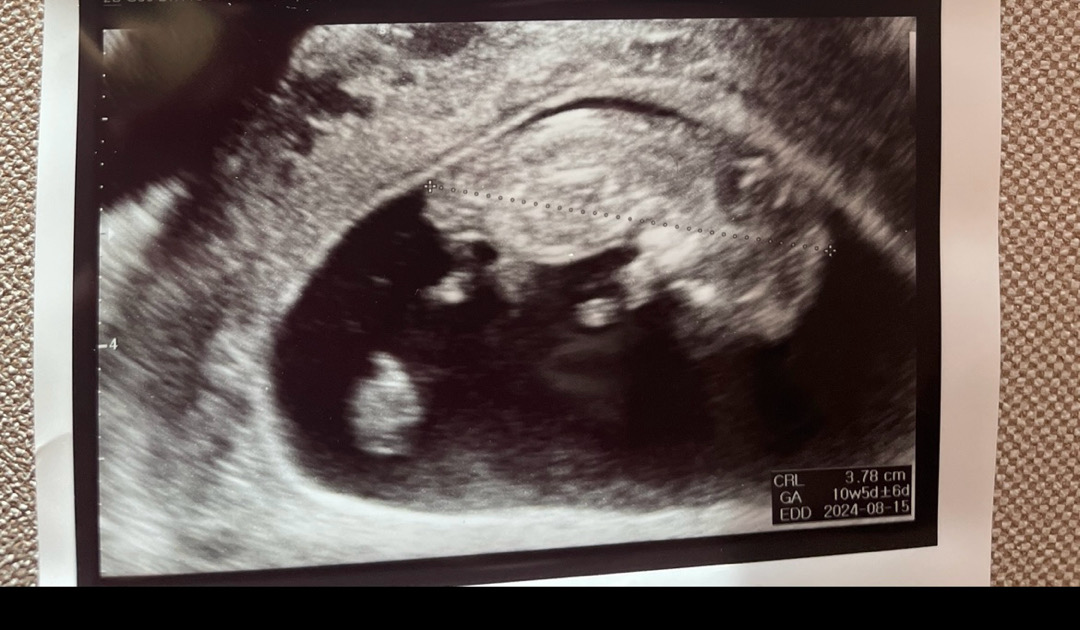

요 사진으로 각도법 볼 수 있을까요?

아직 12주가 아니긴한데 혹시 해서요! 각도법 보일까요?